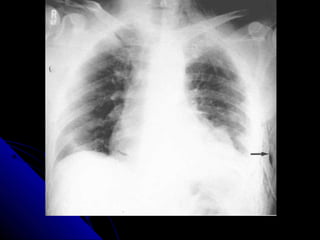

PPnneeuummootthhoorraaxx// tteennssiioonn ppnneeuummootthhoorraaxx..

PPnneeuummootthhoorraaxx// tteennssiioonn

45

ppnneeuummootthhoorraaxx

CChheecckk tthhee tteecchhnniiccaall qquuaalliittyy..

TThhee aabbnnoorrmmaall ssiiddee hhaass << vvaassccuullaarr mmaarrkkiinnggss..

LLooookk ffoorr lluunngg eeddggee..

LLooookk ffoorr mmeeddiiaassttiinnaall sshhiifftt..

AAsskk ffoorr eexxppiirraattoorryy ffiillmm..

PPnneeuummootthhoorraaxx// tteennssiioonn 45 ppnneeuummootthhoorraaxx CChheecckk tthhee tteecchhnniiccaall qquuaalliittyy.. TThhee aabbnnoorrmmaall ssiiddee hhaass << vvaassccuullaarr mmaarrkkiinnggss.. LLooookk ffoorr lluunngg eeddggee.. LLooookk ffoorr mmeeddiiaassttiinnaall sshhiifftt.. AAsskk ffoorr eexxppiirraattoorryy ffiillmm..